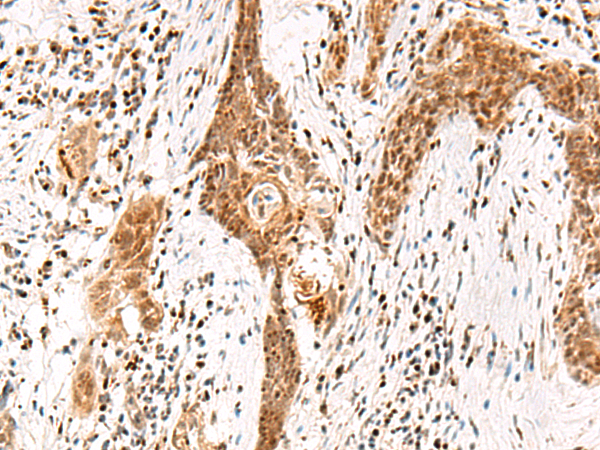

IHC positive control: |

Human thyroid cancer and Human esophagus cancer |

IHC Recommend dilution: |

50-300 |